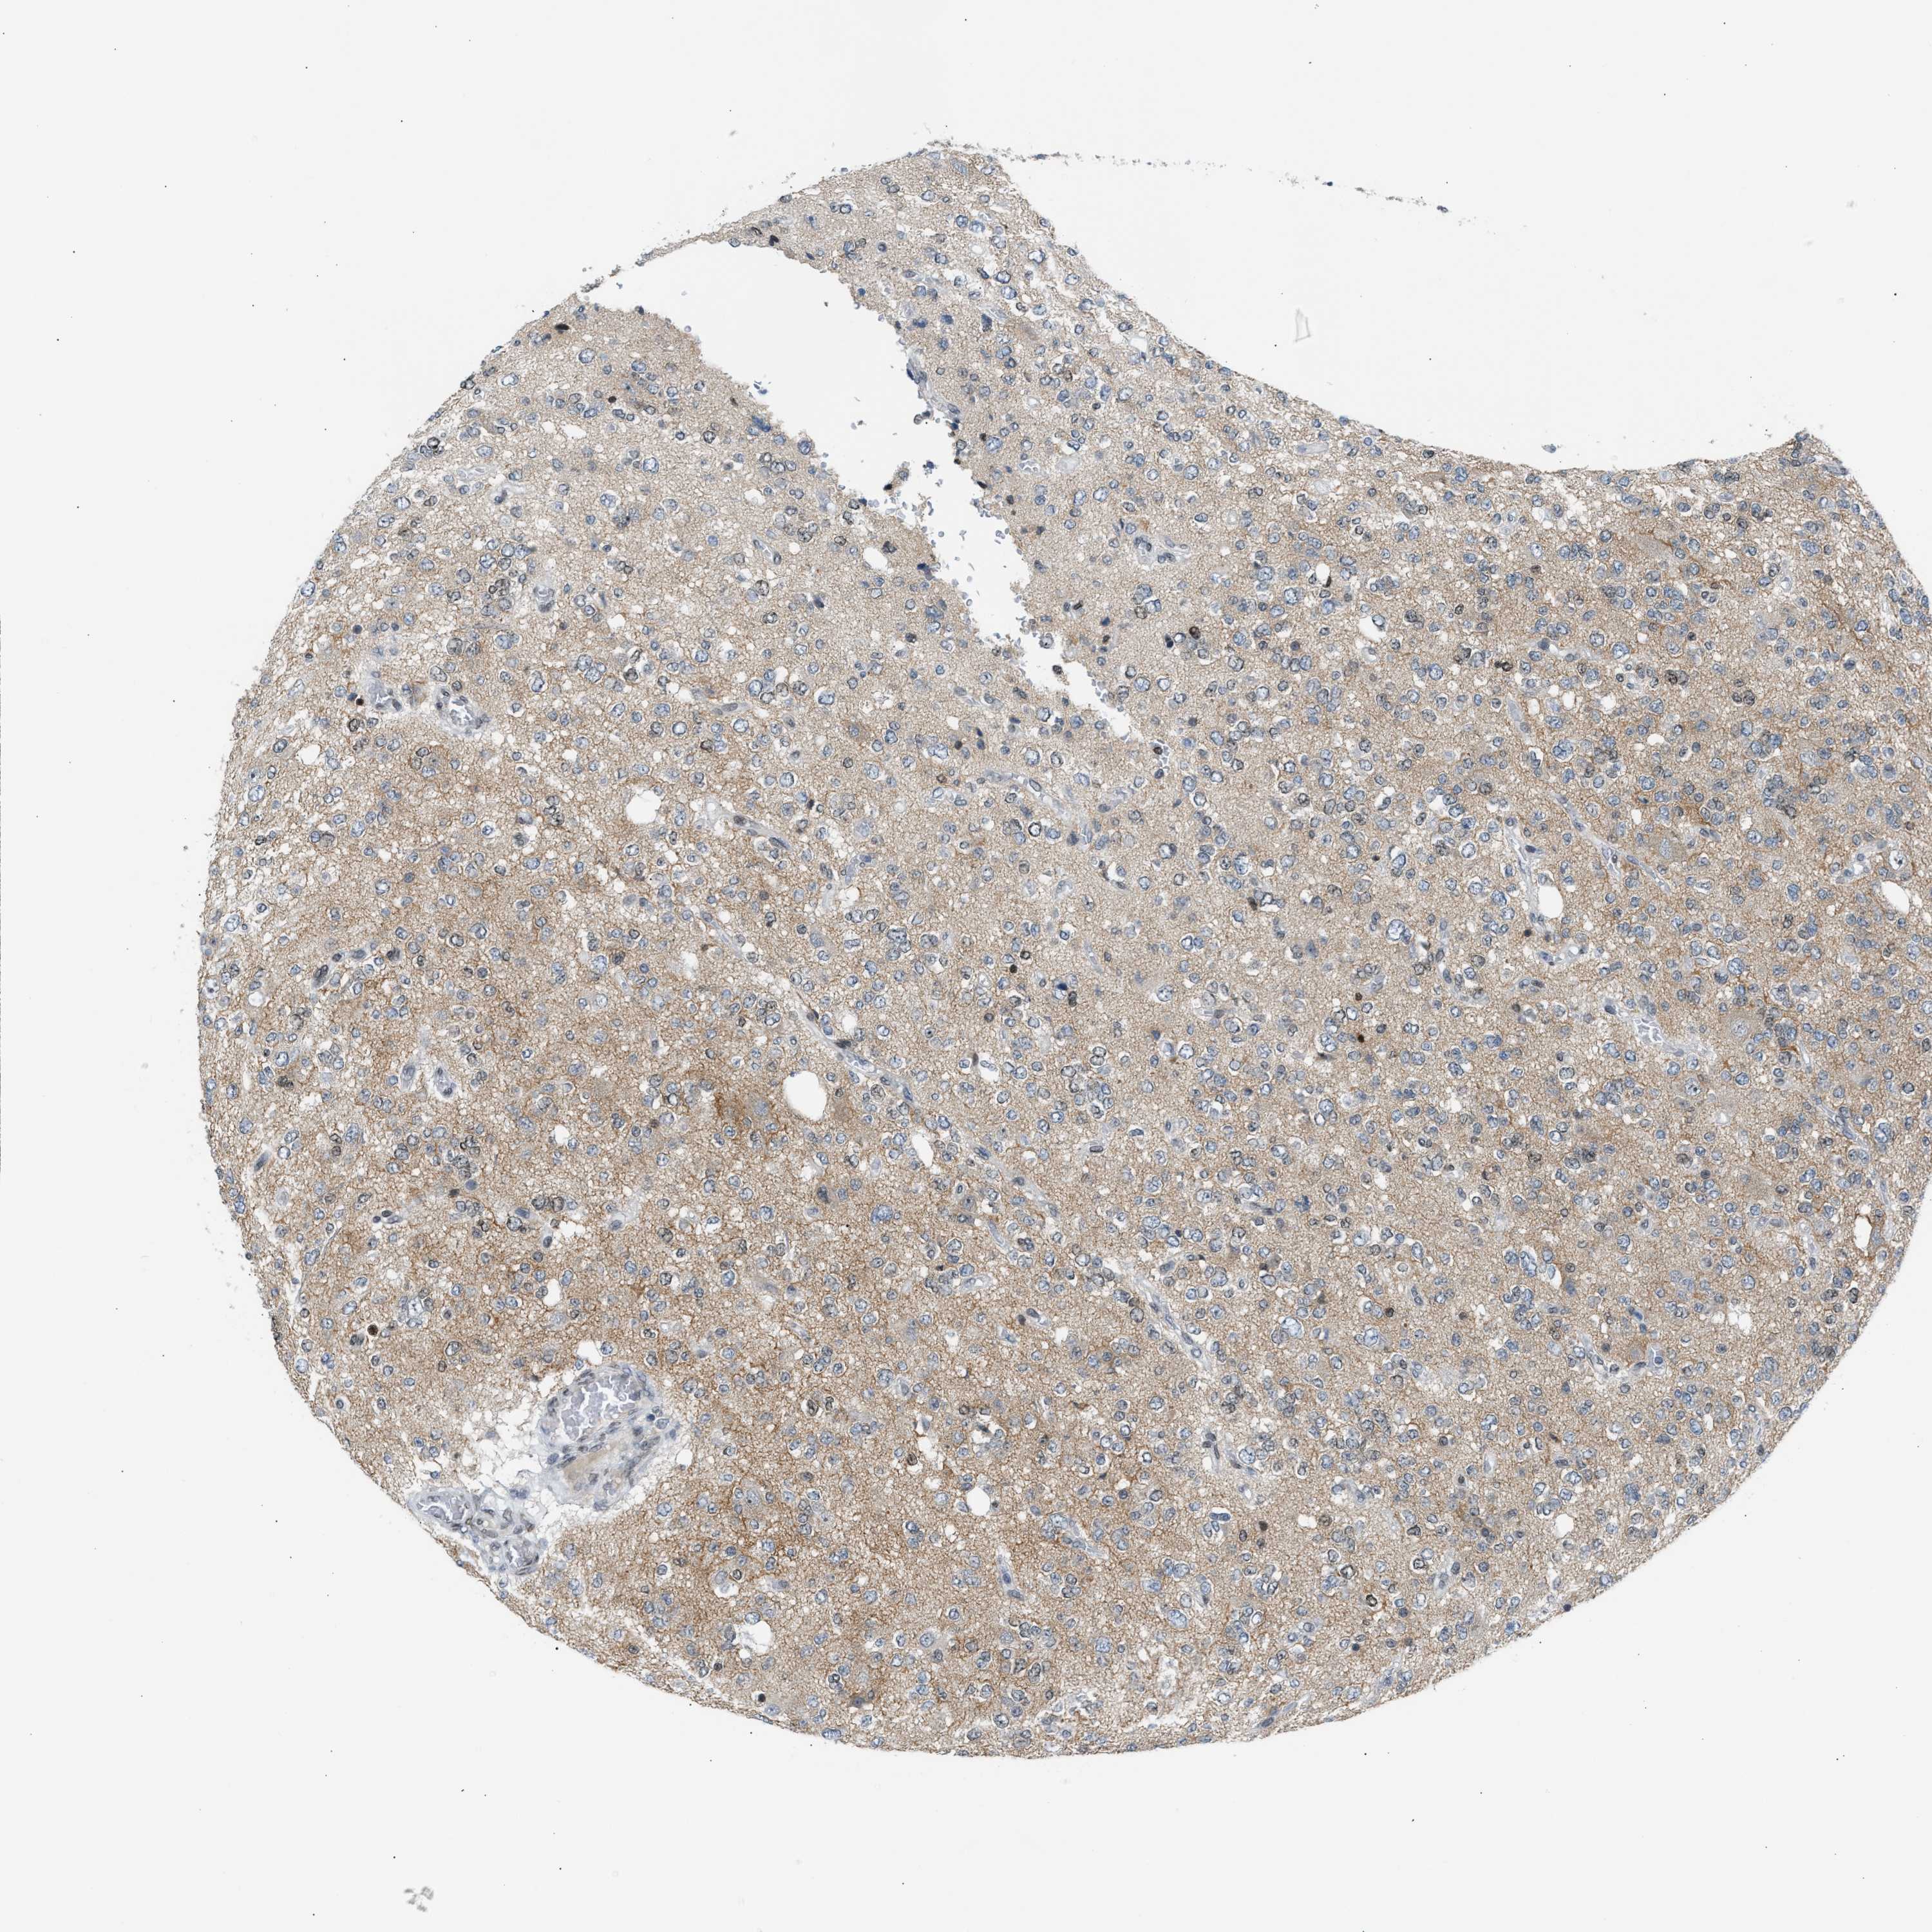

GLIOMA - Protein expressioni

A mouse-over function shows sample information and annotation data. Click on an image to view it in a full screen mode. Samples can be filtered based on level of antibody staining by selecting one or several of the following categories: high, medium, low and not detected. The assay and annotation is described here.

Note that samples used for immunohistochemistry by the Human Protein Atlas do not correspond to samples in the TCGA dataset.

Antibody stainingi

Antibody staining in the annotated cell types in the current human tissue is reported as not detected, low, medium, or high, based on conventional immunohistochemistry profiling in selected tissues. This score is based on the combination of the staining intensity and fraction of stained cells.

Each image is clickable and will lead to virtual microscopy that enables deeper exploration of all samples and also displays staining intensity scores, fraction scores and subcellular localization as well as patient and tissue information for each sample.

Antibody CAB020139

Staining

High

Medium

Low

Not detected

Intensity

Strong

Moderate

Weak

Negative

Quantity

>75%

75%-25%

<25%

None

Location

Nuclear

Cytoplasmic/membranous

Cytoplasmic/membranous,nuclear

Glioma, malignant, High grade

Glioma, malignant, Low grade